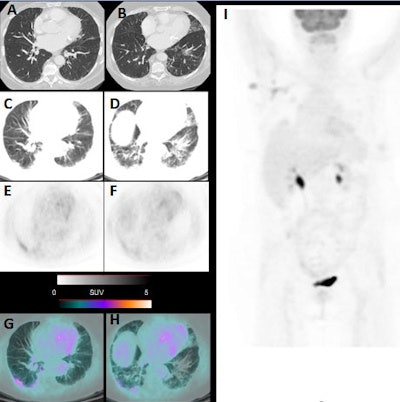

Italian researchers reported that several patients who entered their facility asymptomatic for the novel coronavirus later showed signs of pneumonia on CT and FDG avidity on PET, which made them suspicious for COVID-19. By acting upon the incidental detection of COVID-19 pneumonia in its early stages, subsequent preemptive steps could help prevent the spread of the virus.

Between March 16 and March 24, the nuclear medicine department in Brescia performed 65 FDG PET/CT scans (Discovery ST or 690 scanner, GE Healthcare) for routine oncological indications. All the patients were asymptomatic for the COVID-19 virus, but they were carefully screened before their admittance to the nuclear medicine unit, given the outbreak of SARS-CoV-2 infections in northern Italy. No reason was found to suspect COVID-19 at that time.

Following completion of the scans, six patients (9%) showed signs of pneumonia on CT and FDG avidity in all areas of pneumonia, which made these patients suspicious for COVID-19. The six patients included four women, between 55 and 65 years old, and two men, ages 65 and 77, respectively. When physicians followed up with reverse transcription polymerase chain reaction (RT-PCR) tests, five patients (83%) were confirmed to have COVID-19.